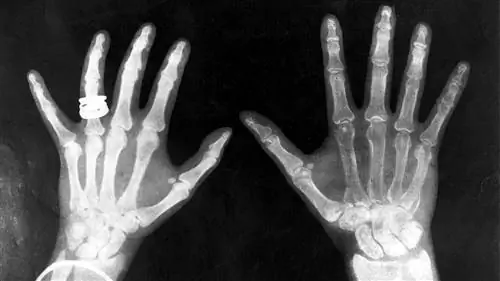

рентгеновские снимки короля Георга и королевы Марии

Рентген помещал между трубкой и экраном разные предметы, а экран все равно светился. Наконец, он поднес руку к трубке и увидел силуэт своих костей, спроецированный на флуоресцентный экран. Сразу после открытия самих рентгеновских лучей он обнаружил их наиболее полезное применение.

Замечательное открытие Рентгена ускорило одно из самых важных медицинских достижений в истории человечества. Рентгеновская технология позволяет врачам видеть прямо сквозь ткани человека, чтобы с необычайной легкостью исследовать сломанные кости, полости и проглоченные предметы. Модифицированные рентгеновские процедуры можно использовать для исследования мягких тканей, таких как легкие, кровеносные сосуды или кишечник.

Мягкие ткани вашего тела состоят из более мелких атомов и поэтому плохо поглощают рентгеновские фотоны. Атомы кальция, из которых состоят ваши кости, намного крупнее, поэтому они лучшепоглощают рентгеновские фотоны.

Как правило, врачи сохраняют пленочное изображение какнегатив То есть области, подвергающиеся большему воздействию света, кажутся темнее, а области, подвергающиеся меньшему воздействию света, кажутся светлее. Твердый материал, например кость, выглядит белым, а более мягкий материал - черным или серым. Врачи могут сфокусировать различные материалы, изменяя интенсивность рентгеновского луча.